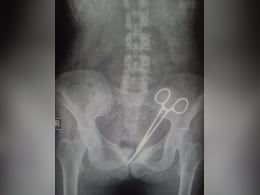

डॉक्टरों की गंभीर लापरवाही: सर्जरी के बाद महिला के पेट में 12 साल तक पड़ी रही सर्जिकल कैंची!

एक महिला के पेट में 12 साल तक कैंची (Surgical scissors) पड़ी रही और इस लंबे समय में डॉक्टर इसका पता नहीं लगा पाए, जबकि महिला इतने साल तक पीड़ा सहती रही. सिक्किम (Sikkim) में यह मामला सामने आया है. डॉक्टरों ने 12 साल पहले सर्जरी में लापरवाही बरती थी और कैंची पेट में छोड़ दी थी. अब 12 साल बाद जब पता चला तो डॉक्टरों ने पेट की सर्जरी करके कैंची निकाल दी है.

ब्राजील में सर्जरी कर डॉक्टरों ने एक नेता के पेट में कैंची छोड़कर लगा दिए टांके, 6 दिन बाद निकाली बाहर

ऑपरेशन के छह दिन बाद बीमार महसूस करने के बाद राजनेता (Politician) को एहसास हुआ कि कुछ गड़बड़ है. सीटी स्कैन करने के बाद उनकी आंतों के अंदर कैंची (Scissors) की एक बड़ी जोड़ी पाई गई.